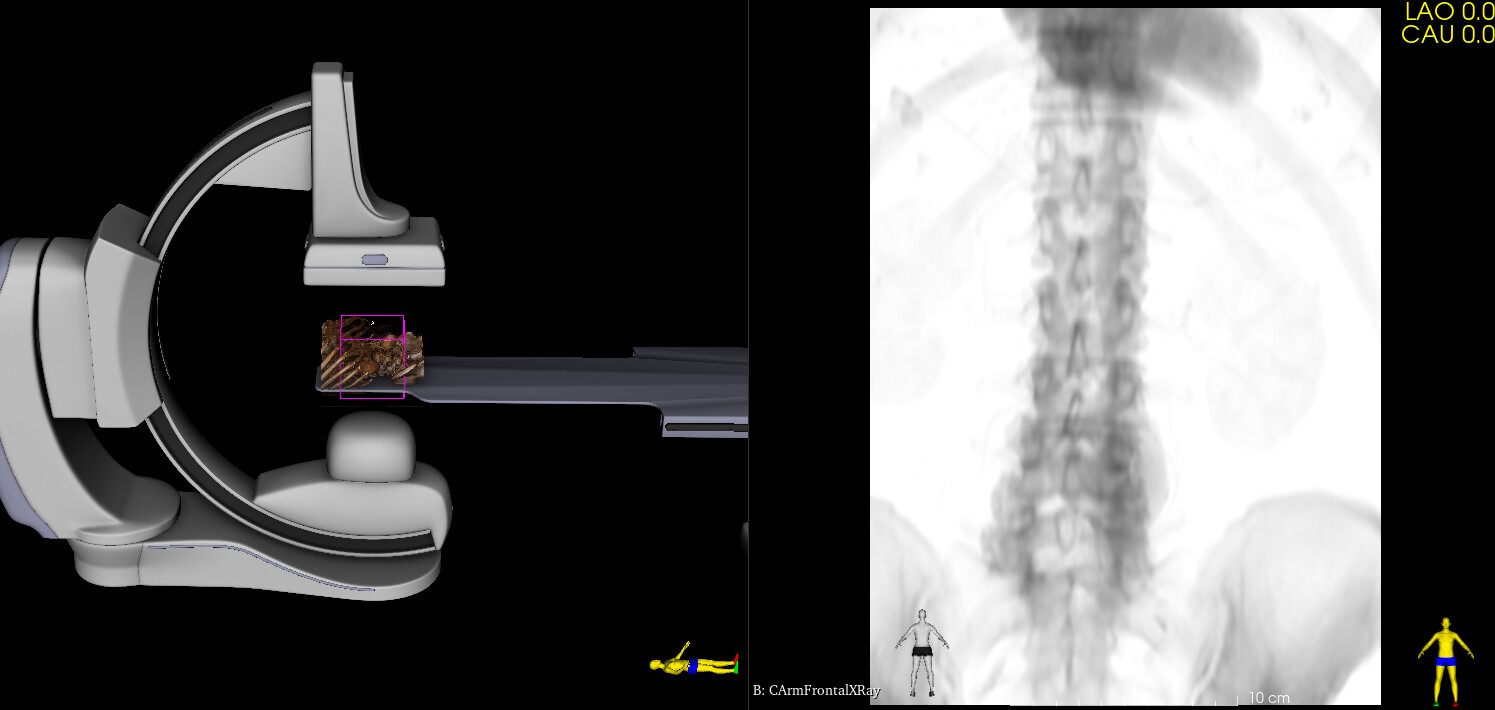

Virtual Cath Lab module has been recently added to SlicerHeart extension. This module simulates monoplane and biplane C-arm systems: provides 3D model of the C-arm, table, patient and generates simulated fluoroscopy images. Images can be either static (generated from 3D CT) or dynamic (generated from 4DCT). The module can also display cardiac devices (stents, occluders, clips, etc. provided by the Cardiac Device Simulator module) and virtual contrast filling (from image segmentation).

The module was developed for cardiac and vascular procedures, but it is well suited for simulation of any fluoroscopy guided procedures.

I’ve updated the module with the followings:

• Added detector rotation angle (no auto-rotation is available, but the rotation can be easily manually adjusted on the GUI)

• Default L arm angle is set the C-arm to be at the side of the table

• Projection beam is displayed (to make it easier to see the field of view in 3D)

• Detector size is configurable in the preset .csv files

It is indeed much better and more realistic to OR situations. I’ll give more feedback

later on cumulating experiences on more cases. Thank you very much.